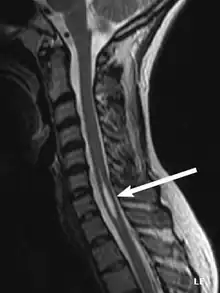

An idiopathic syrinx

Physicians now use magnetic resonance imaging (MRI) to diagnose syringomyelia. The MRI radiographer takes images of body anatomy, such as the brain and spinal cord, in vivid detail. This test will show the syrinx in the spine or any other conditions, such as the presence of a tumor. MRI is safe, painless, and informative and has greatly improved the diagnosis of syringomyelia.[19]